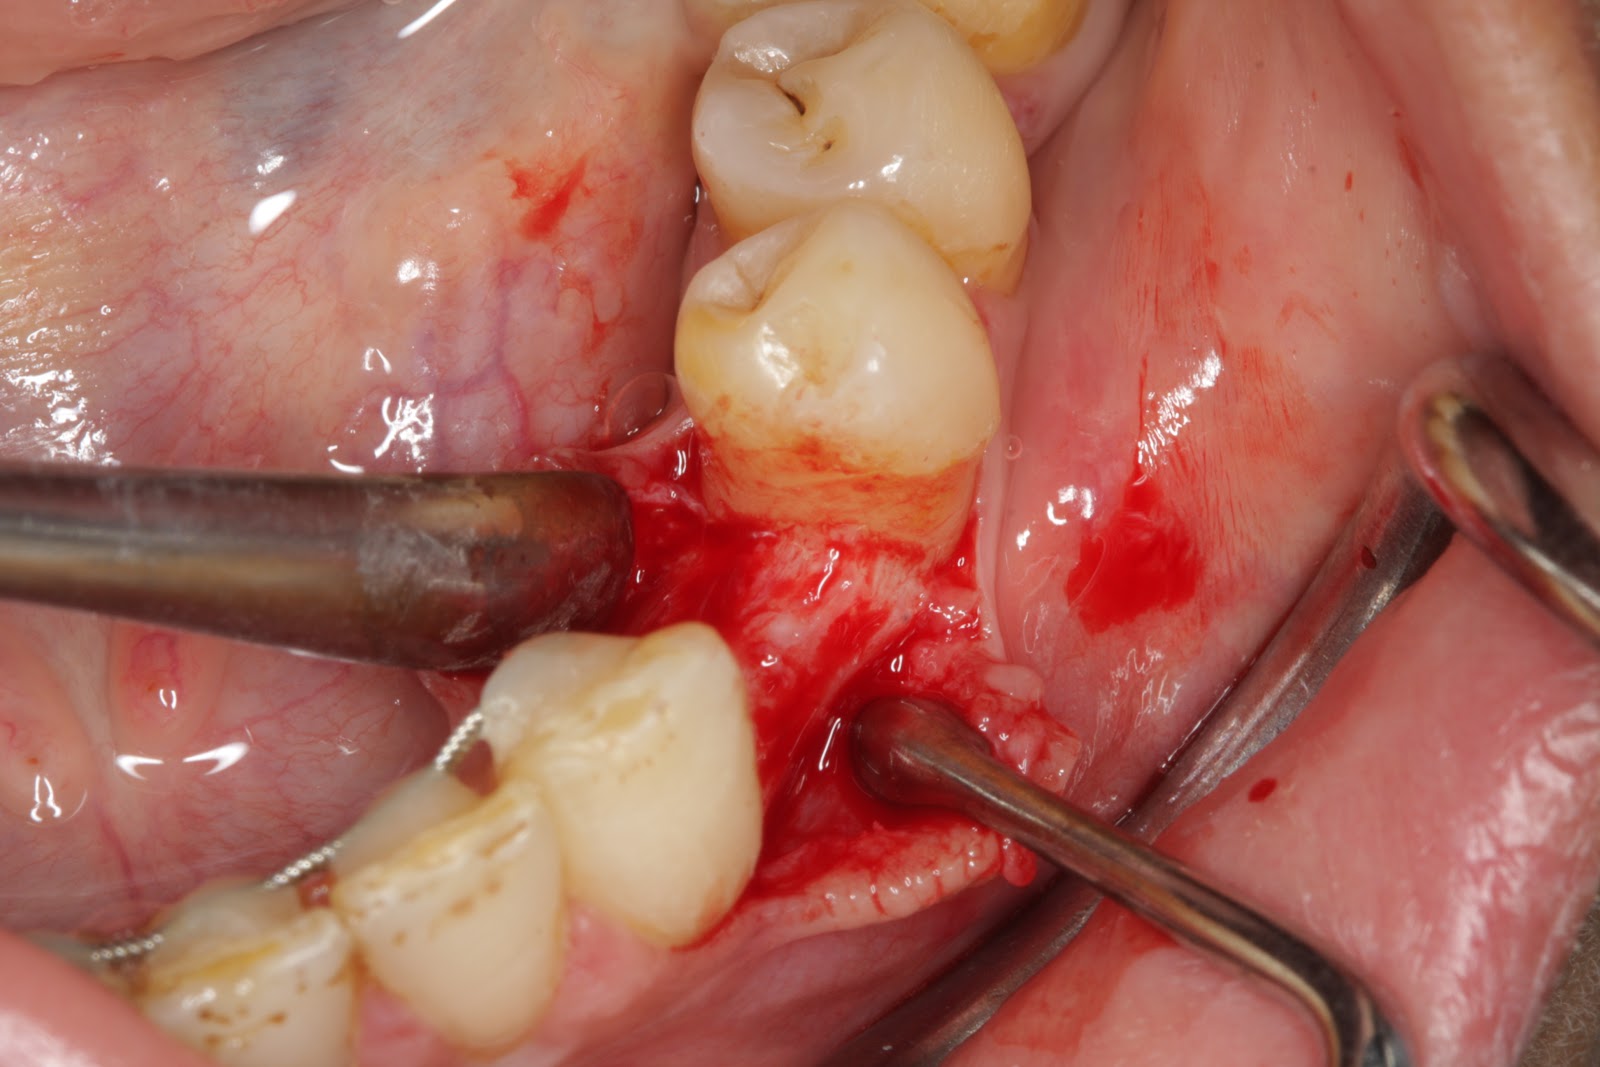

Extraction/bone Grafting And Membrane Placement Post ...

Extraction/bone grafting and membrane placement post-operative instructions Antibiotic If an antibiotic has been prescribed, start taking it the first day (unless directed otherwise) ... Read More